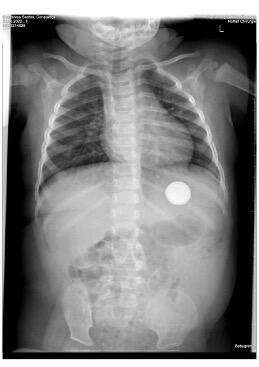

An 11-month-old girl is presented at the emergency department 3 hours after ingesting a button shaped battery, without any symptoms. On physical examination the patient is completely fine without any abnormalities. An X-ray of the abdomen was performed and shows the image below.

The patient ended up presenting herself to the outpatient clinic 4 days following the ingestion of the battery, still asymptomatic. A new X-ray of the abdomen showed that the battery hadn’t moved. We noticed the battery still in the stomach, therefore we referred the patient to the gastroenterologist for the next available appointment for an endoscopic removal of the button battery from the stomach. A few days later, another X-ray showed the battery had moved to the intestines. Subsequently the endoscopy was cancelled, and the battery came out via natural way within a few days.